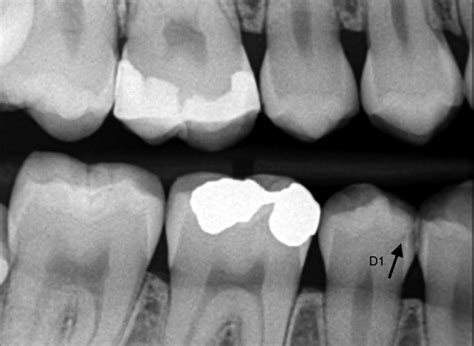

Caries en la infancia: Un problema común

Una caries es una lesión en el diente causada por la descomposición de los tejidos debido a la presencia de ácidos producidos por bacterias en la placa dental. En la infancia, las caries pueden desarrollarse tan pronto como erupcionan los primeros dientes, lo que destaca la importancia de una buena higiene oral y prácticas dietéticas saludables desde temprano. Por eso, es vital acudir a revisiones periódicas con el odontopediatra.